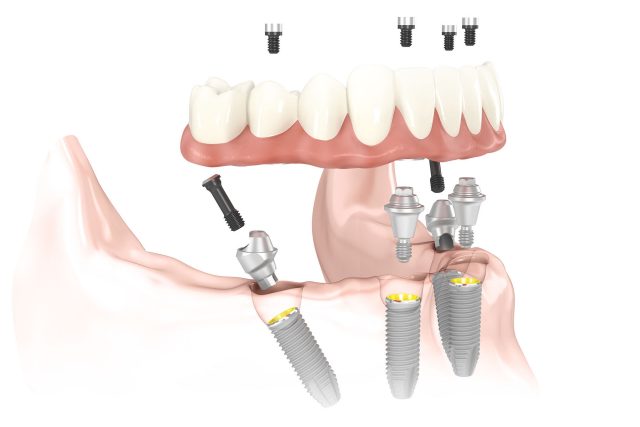

Implantologia dentale

Protesi